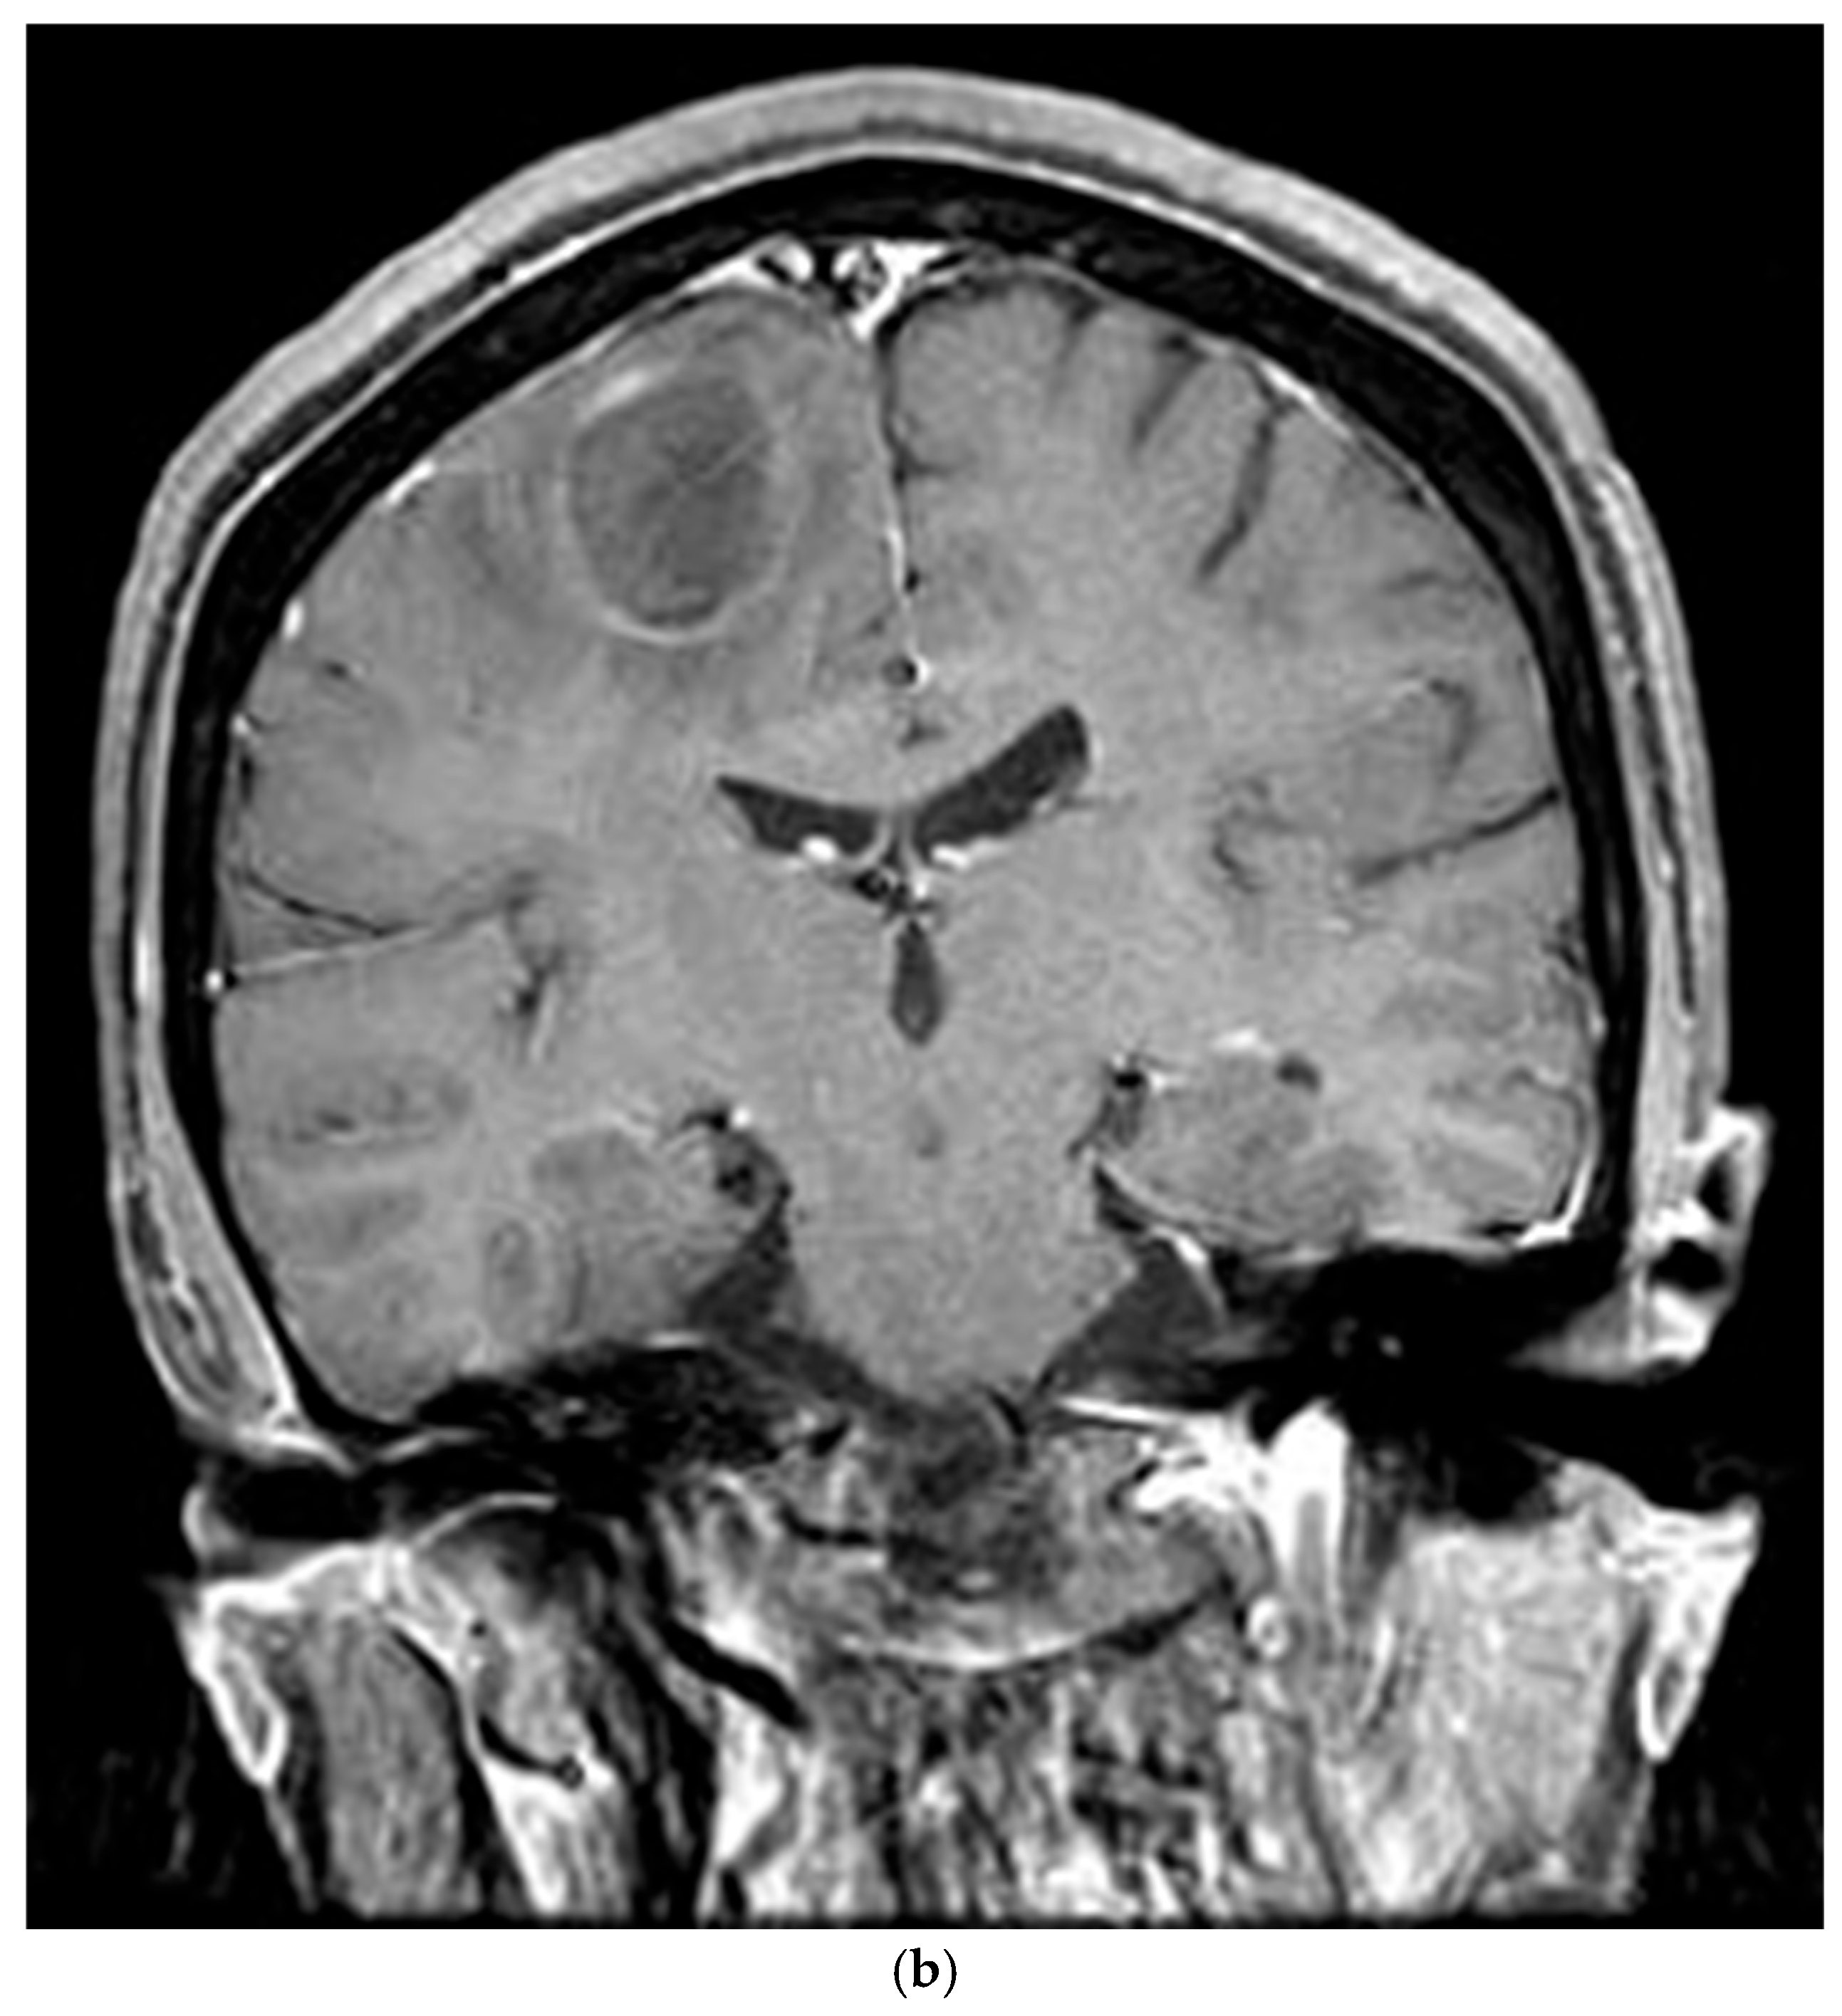

The patient’s postoperative period was uneventful, and she was discharged and subsequently administered chemotherapy. However, three months later, the patient was readmitted with left-sided hemiparesis. Brain MRI revealed a 25 mm T2-high signal and T1-low signal intensity mass with perilesional edema and faint peripheral enhancement in the posterior portion of the right superior frontal gyrus (Figure 6). Stereotaxic biopsy of the brain mass confirmed metastasis from the primary lung tumor. The metastatic brain tumor with hemorrhage was surgically removed, and the patient was started on chemotherapy and radiotherapy.

Figure 6.

Three-months postoperative coronal (a) T2 and (b) enhanced T1 images revealed a hemorrhagic rim-enhancing mass with perilesional edema in the right frontal lobe.